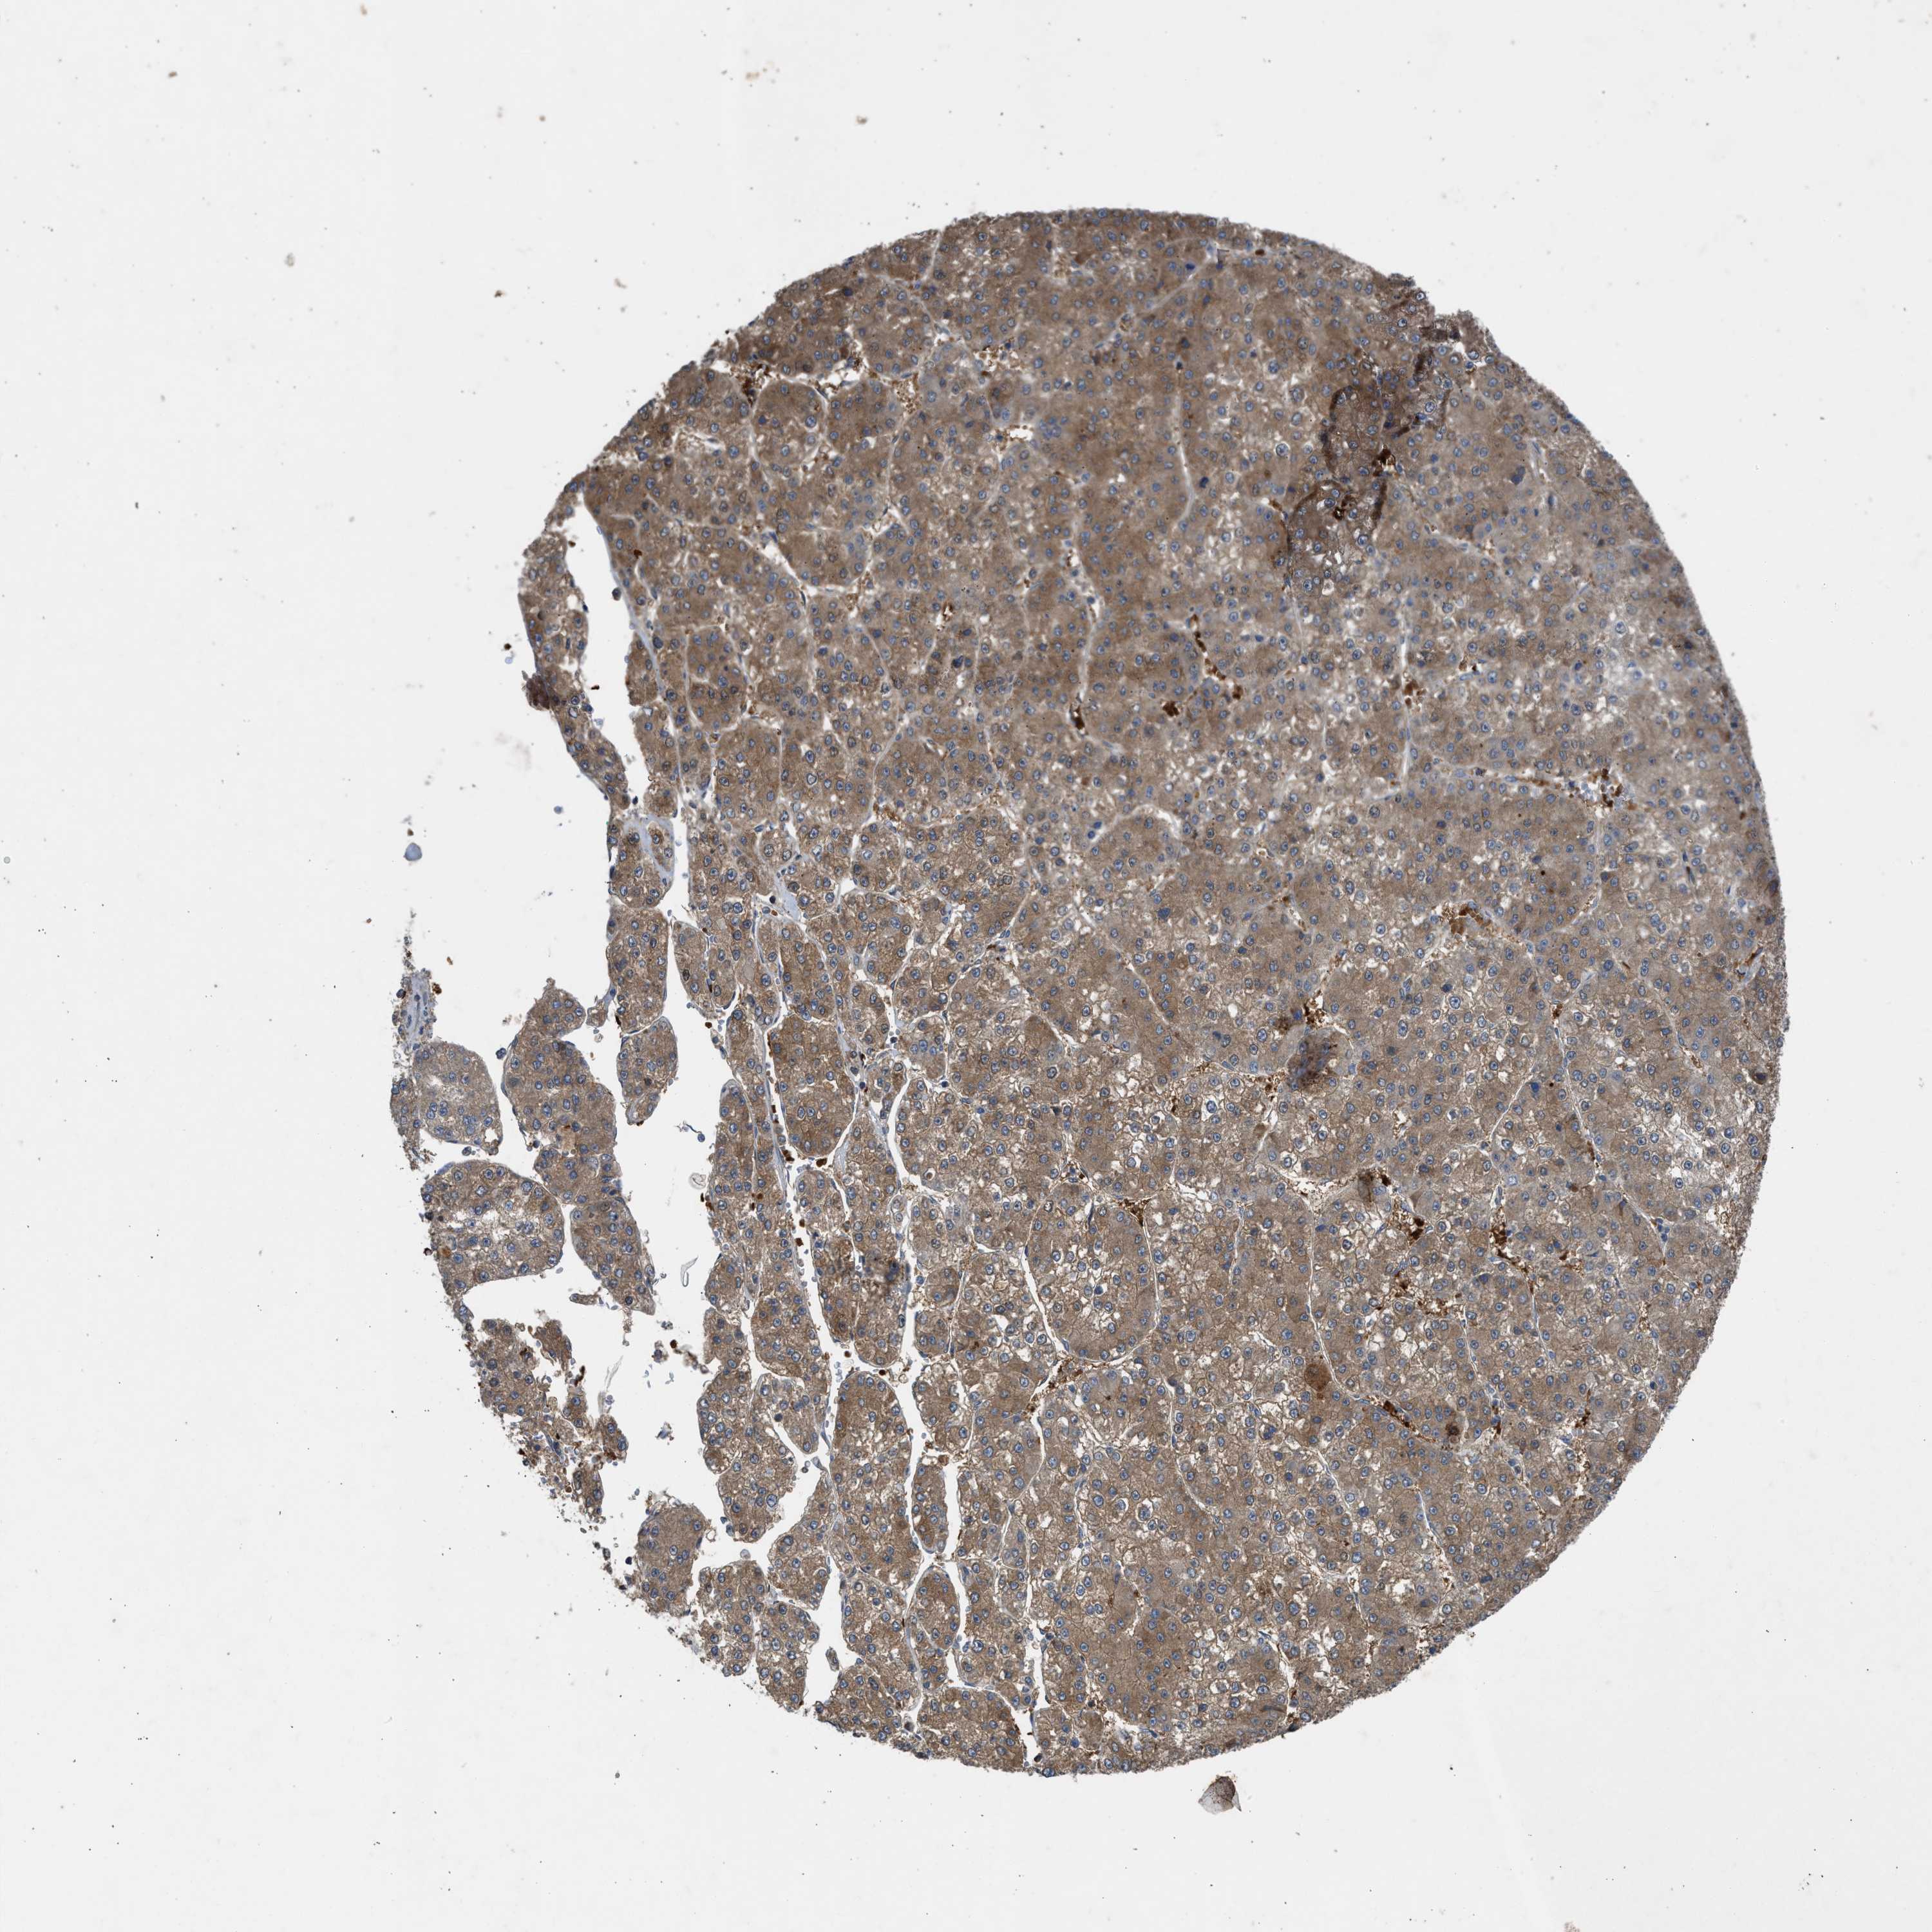

LIVER CANCER - Protein expressioni

A mouse-over function shows sample information and annotation data. Click on an image to view it in a full screen mode. Samples can be filtered based on level of antibody staining by selecting one or several of the following categories: high, medium, low and not detected. The assay and annotation is described here.

Note that samples used for immunohistochemistry by the Human Protein Atlas do not correspond to samples in the TCGA dataset.

Antibody stainingi

Antibody staining in the annotated cell types in the current human tissue is reported as not detected, low, medium, or high, based on conventional immunohistochemistry profiling in selected tissues. This score is based on the combination of the staining intensity and fraction of stained cells.

Each image is clickable and will lead to virtual microscopy that enables deeper exploration of all samples and also displays staining intensity scores, fraction scores and subcellular localization as well as patient and tissue information for each sample.

Antibody CAB018561

Staining

High

Medium

Low

Not detected

Intensity

Strong

Moderate

Weak

Negative

Quantity

>75%

75%-25%

<25%

None

Location

Nuclear

Cytoplasmic/membranous

Cytoplasmic/membranous,nuclear

Cholangiocarcinoma

Carcinoma, Hepatocellular, NOS